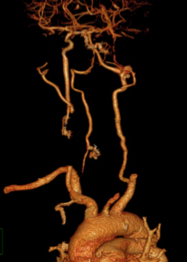

CT scanner angiography of brain revealed that there was no imagine of Left ICA as well as no hemorrhage. The patient was asumpted to have acute cerebral infarction in a situation of peri- endarterectomy surgery, that meaned this was an unknown onset stroke

The DSA imagine showed a totally occlusion from the Left CCA. Assumpting that this must be a dissection lesion, carotid stenting was perform with 2 Carotid stent 8x40mm from CCA up to ICA after a loading dose of DAPT. After procedure, the patient was recovery at mRS of 1.